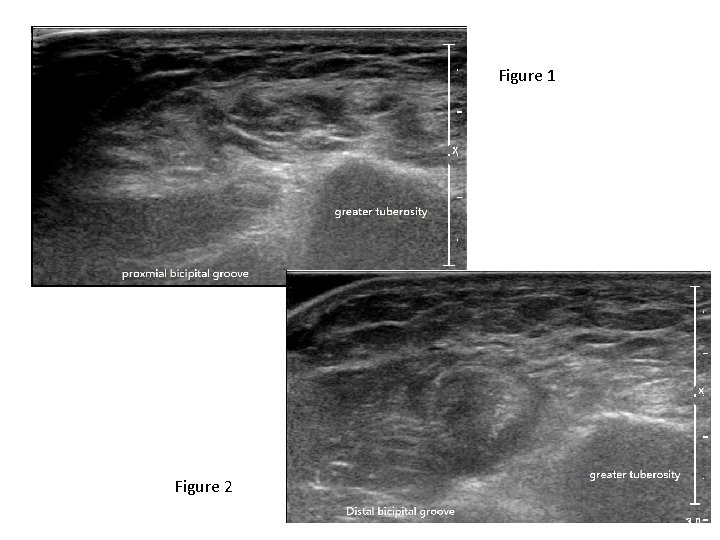

Case 5 • M/35 • Amateur body builder • c/o sudden sharp pain in

Case 5 • M/35 • Amateur body builder • c/o sudden sharp pain in left upper arm while practicing weight lifting

Questions • Describe the abnormality showed in the clinical photo • What was the

Questions • Describe the abnormality showed in the clinical photo • What was the sign called? • What bedside investigation would help in diagnosis in ED?

Figure 1 Figure 2

• Describe the ultrasound findings

• What was the diagnosis? • What were the management options for the

• What was the diagnosis? • What were the management options for the patient?